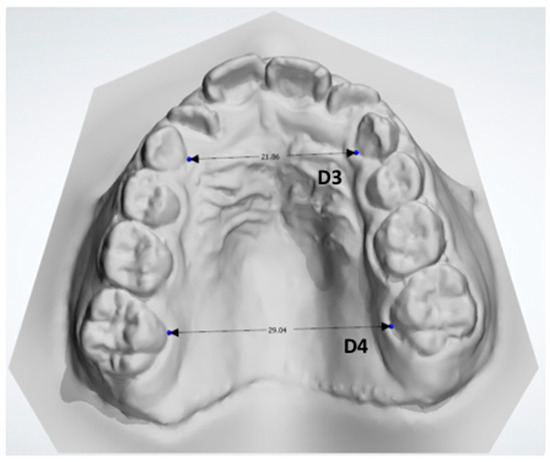

- D3: the distance between the midpoint at the dento-gingival junction of the two primary canines (Figure 7).

- D4: the distance between the midpoint at the dento-gingival junction of the two first molars (Figure 7).